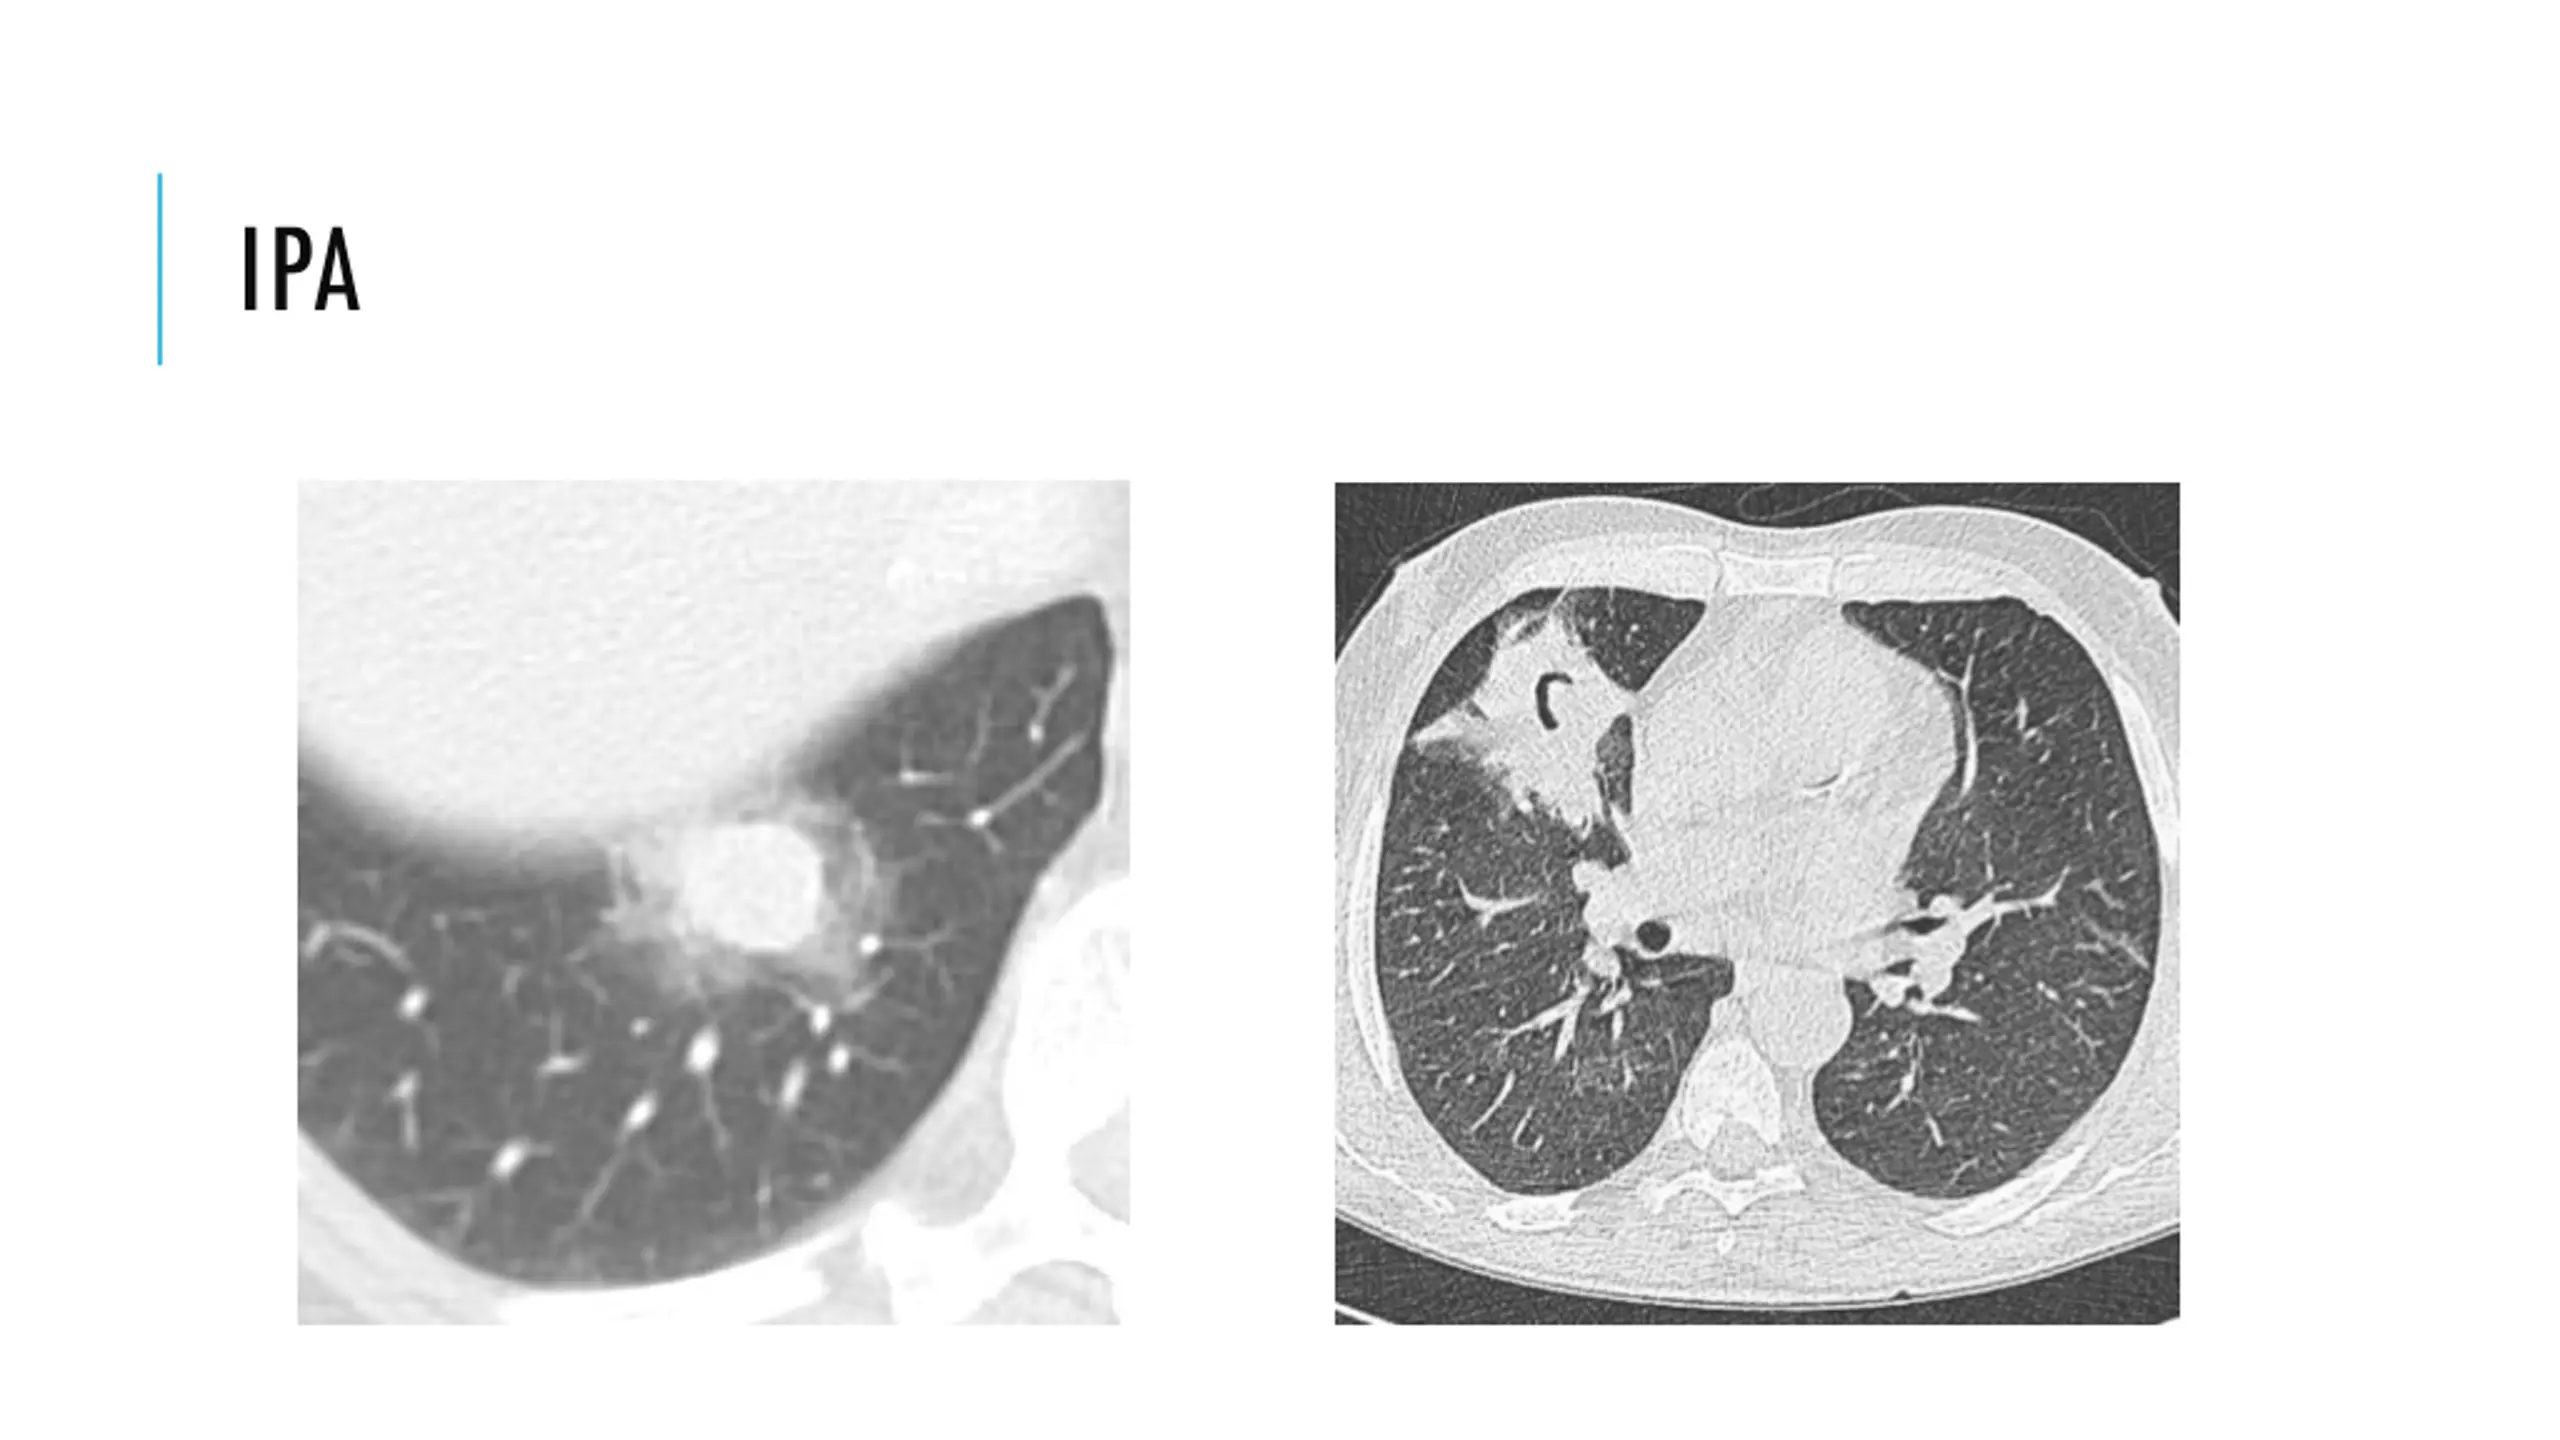

8. INVASIVE PULMONARY ASPERGILLOSIS (IPA) Neutropenia most important risk factor Risk goes up as neutropenia continues (1%/day for first three weeks, then up to 4%/day thereafter) Present vaguely (fever, productive cough, dyspnea, chest pain with infarcts, hemoptysis) Spreads hematogenously (mostly to brain) CT with nodules, halo sign, and air-crescent sign Diagnosis: Fungal stain and culture (wash or tissue). Serum or BAL galactomannan Treatment: Voriconazole (6mg/kg IV q12h x1 day, then 4mg/kg IV q12h, then 200mg orally q12h) x3 months Consider surgery

9. IPA